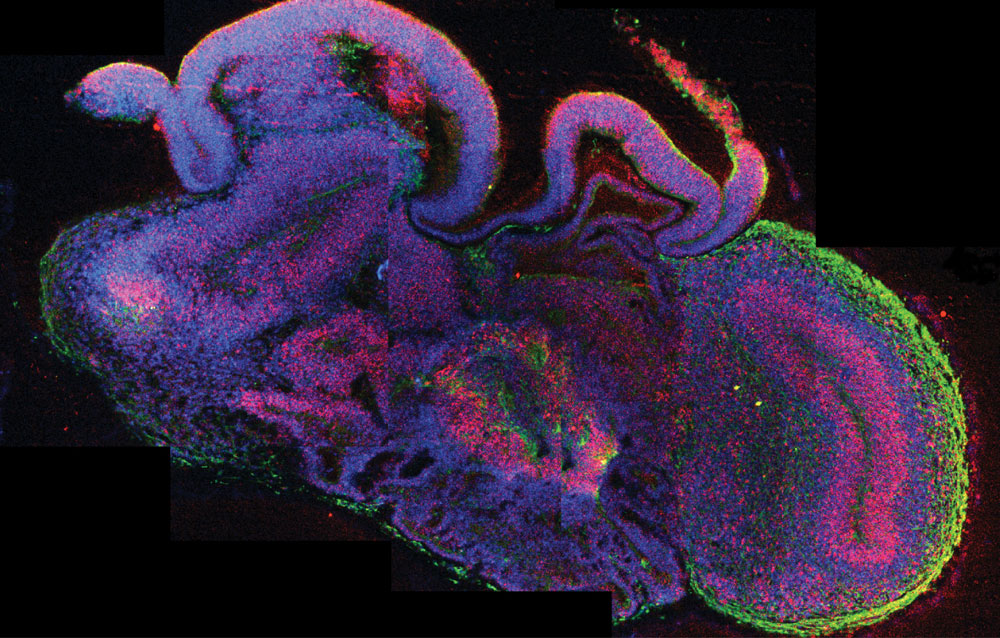

FOTO: Madeline A. Lancaster (NATURE)

Microcerebros a partir de células madre

¿Puede crearse una mente en el tubo de ensayo? El cerebro era hasta ahora la línea roja en la tecnología de generación de órganos a partir de células madre, pero este año se saltó al cultivarse en el laboratorio vienés unos minicerebros humanos, u organoides cerebrales del tamaño de un guisante, que desarrollan espontáneamente las estructuras y capas neuronales del córtex, la sede de la mente humana.